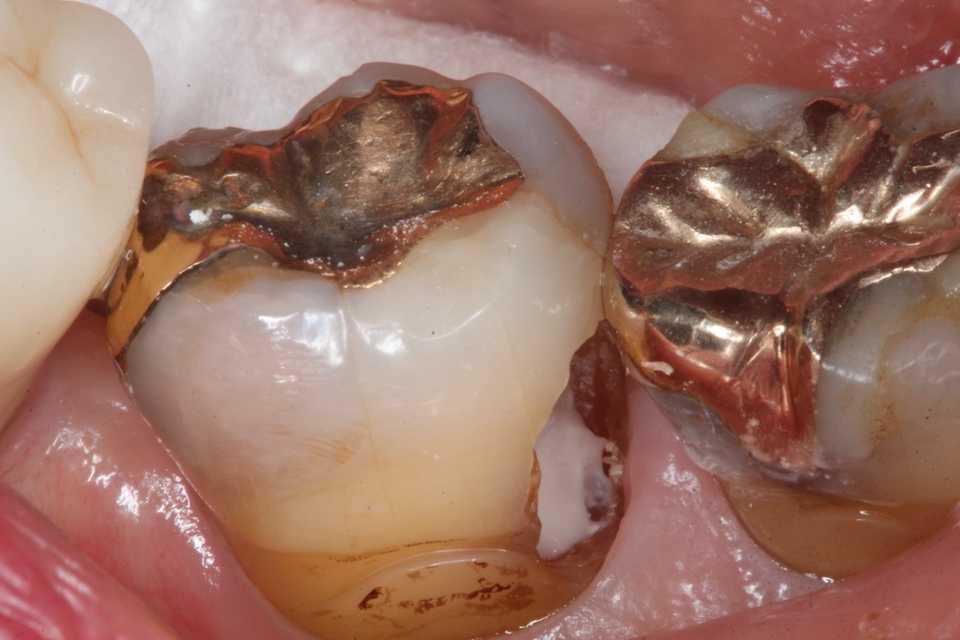

これが処置前の画像。亜鉛華ユージノールセメント貼付などの処置はしないで欲しいというのが本音。